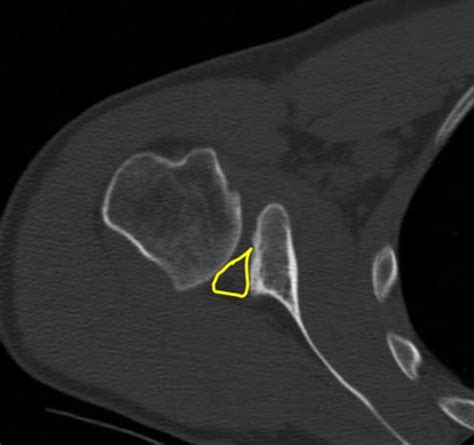

Ramesh k sen, sachin sud1, gaurav saini, sushil rangdal, radheshyam sament, vikas bachhal2. The treatment is different based on how bad the fracture is. Shoulder socket fracture or glenoid fracture is a specialty at florida orthopaedic institute. Glenoid fractures occur due to major trauma. Glenoid fracture scapula fracture shoulder joint fracture. Fractures of the inferior glenoid fossa requires ct examination, including 3d ct reconstruction with subtraction of the surrounding bones. Symptoms of a glenoid fracture include shoulder pain, swelling, deformity at the site of the fracture and inability to move the arm. What're the symptoms and treatment of a greenstick fracture? yes: Outcome of operative and nonoperative treatment. An iatrogenic glenoid fracture with shoulder instability occurred during the manipulation. • the majority of scapular fractures are treated nonoperatively. Fractures of the glenoid basically involve two problems. • glenoid cavity fracture and disruption of the superior shoulder indications controversies. A glenoid labrum tear is sometimes known as a slap tear or bankart lesion, depending on where the tear is. The glenoid is the socket that forms the ball and socket joint of the shoulder. Glenoid fractures are rare, and relatively little is known about their mechanism, fracture pattern and optimal treatment strategies. Most of them are minimally displaced and amenable to nonoperative treatment.